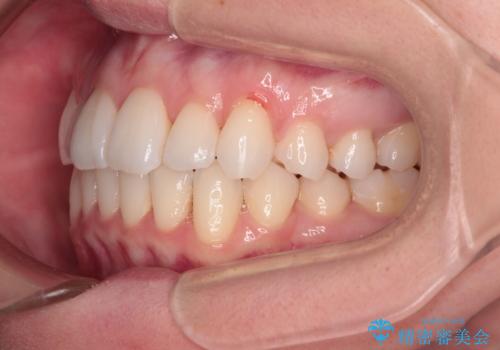

【モニター】インビザラインで気になるデコボコと八重歯をきれいに整える

- 上下前歯のデコボコ、特に右上の八重歯を気にして来院された患者様です。

妊娠、出産の予定があり、毎月の通院が困難となる可能性があったため、インビザラインによる矯正治療を行うこととしました。

事前に親知らずを抜歯しておき、出産時期に困ることのないように準備をした上で治療を開始しました。

治療後半では悪阻によりマウスピースの装着時間が不十分となることもありましたが、それよりも前にしっかりと装着時間を守って治療を進めることができたため、特に気になるところなく治療を終えることができました。